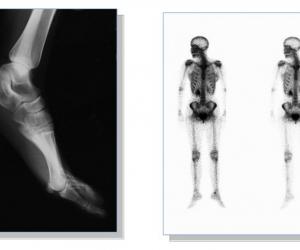

自从X光在1895年被发现后,医学界便广泛利用它作诊断用途。X光拥有能穿透物质的特性,相同的X光能量,对于不同密度的物质,有不同的穿透能力。因为人体的器官及骨骼有着不同的密度,当X光投射及穿透人体某个部位后,便能在菲林(X光片)上造成深浅不同的影像。这些影像对于病症诊断有很大的帮助,最常见的检查是应用于诊断骨折(fracture)及肺部的疾病上。近年,一些介入性(interventional)而有治疗作用的X光检查,也很普遍。根据统计,医疗诊断仪器中, X光的使用便占了百分之六十。 X光在医学发展历史中扮演了举足轻重的角色,从小诊所到大医院, X光造影通常是第一线的诊断工具, 当 X射线穿过物质时,会产生两种物理现象; X光的吸收与折射。传统的 X光造影呈像,是利用射线穿过不同物质吸收时,在底片表现出的灰白色阶影像,通常影像的对比及分辨率较差。传统的 X光诊断,有其技术上与安全上尚未突破的盲点,特别是软组织病变的侦测,因此研究者从 X光的物理特性来试着改善目前医疗诊断所遇到的瓶颈。于是部分的研究学者开始探讨有关 X光折射在医学影像的应用,希望透过不同的成像方式,可以得到理想的诊断结果。 在瑞士洛桑(Lausanne)Ecole Polytechnique Federale的 Giorgio Margaritondo教授和他的同僚,发展了一项根据 X射线折射为理论基础,对全身造影的新技术。他们认为这项科技,有机会取代计算机断层与核磁共振仪在现今医疗诊断的功能。折射现象发生在 X射线或其它的电磁波,例如光线等穿过不同介质,行径方向改变的一种物理现象,折射的角度取决于行径不同的两种介质组成。当 X射线穿过身体,经过不同的组织、器官后,会呈现多变化的折射现象,这复杂的折射纪录透过计算机的运算,可以计算出身体中目标物体的密度与位置,相较于传统的 X光诊断,这种利用折射原理所产生的相对比 (phase-contrast)技术,其优点在于得到更精确清晰的造影,并且可以快速的照像而形成电影般的纪录,甚至可以应用在个别细胞及基本结构的观察。 临床上使用的 X光源为全方向的扩散,然而这项科技的缺点是因为所处理的信息中所包含的几何光束,需要在 X光起始的方向上作精准的连结,达到一致的相位。目前研究小组利用同步幅射仪的磁场中,高能电子所产生连续的 X射线来进行研究,但同步辐射仪体积庞大,使用金额高,无法使用于例行性的临床研究上。 传统的 X光诊断中,辐射是最令人担心的问题,尤其越精密的检查需要越高剂量的 X射线,但高剂量幅射容易导致癌症的发生与恶化,进而降低了民众检查的意愿。目前瑞士研究小组正利用相比对技术进行小动物、昆虫及鱼类的临床实验,而意大利的研究团队,希望能够将这项技术应用在乳癌的筛检。不仅是因为这项科技的准确性,能够克服传统 X光技术在软组织诊断上的不足,降低诊断潜在的危险,得到更准确的检查结果,未来甚至可以应用在更多疾病例如心血管病变的诊断上,让这些例行性的检查,更具有安全性与准确性。 一些人体骨骼的X光照片 |